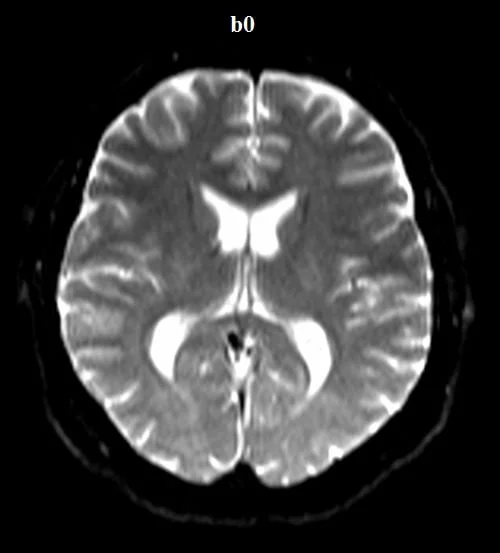

Diffusion-weighted (DWI) axial sequences with b-factors of b0, b500, and b1000 are used in brain imaging.

b-value 0

DWI (Diffusion-Weighted Imaging) images with b0 and b1000 values in MRI provide distinct information about tissue characteristics.

- b0 Image: The b0 image, often referred to as the “baseline” image, is acquired with no diffusion weighting. It captures the inherent signal intensity of tissues without directional sensitivity to water diffusion. In the b0 image, tissues appear with their natural signal intensity, resembling T2-weighted images. This image serves as a reference for comparison with diffusion-weighted images.